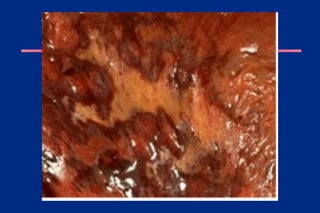

The thrombus looks like